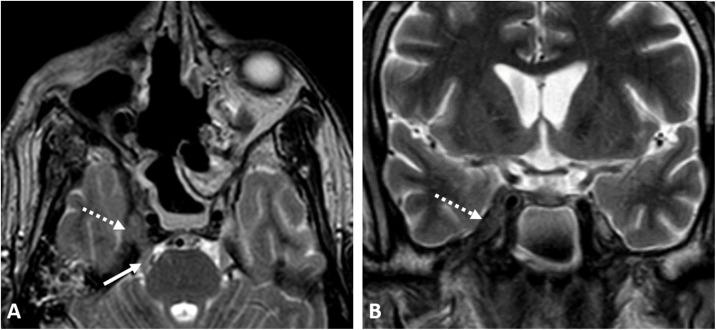

This is a case series presenting the radiologic features and clinical presentation of acute invasive fungal rhino-orbital-cerebral sinusitis (AIFS) in eight hospitalized patients with confirmed COVID-19 infection.

Our patient cohort presented with symptoms of the invasive fungal disease within 12-35 days from their initial presentation with COVID-19 infection. The cross-sectional imaging features of AIFS associated with COVID-19 infection do not differ from those reported in the literature for AIFS associated with other risk factors, yet our patients had features of aggressive late-stage forms with high morbidity and mortality rate.